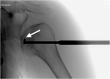

Osteonecrosis of the humeral head is an uncommon condition, and treatment options are controversial. The shoulder is the second most common location for osteonecrosis, typically presenting between the second and fifth decades of life. Early diagnosis and treatment are essential because osteonecrosis may progress and lead to significant pain and loss of function. Nonoperative options are limited and are based on addressing the cause of the osteonecrosis. Multiple surgical treatments have been described, and these techniques continue to evolve. Open core decompression of the humeral head has been found to be an effective surgical option to restore blood supply and stimulate new bone formation. The evolution of arthroscopic techniques combined with biological adjuncts allows a minimally invasive approach with potential to accelerate revascularization and bone growth. We describe our technique for arthroscopic-assisted intraosseous bioplasty of the humeral head for the treatment of osteonecrosis.